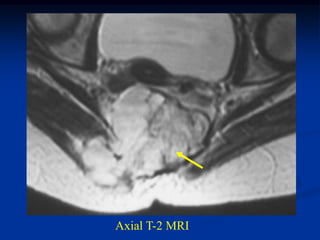

Case #1096

18 year male with

adamantinoma tibia

Bone scan

Sagittal T-2 MRI

Axial T-2 MRI